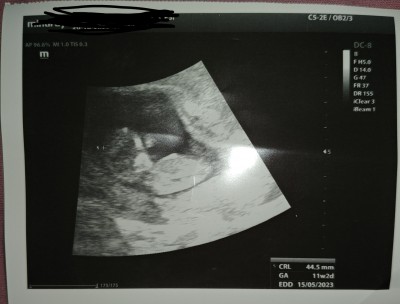

Merhabalar aramızda cinsiyetten anlayan varsa memnun olurum☺️

Gebelik haftası 13.hafta

Cnm erkeğe benziyor hayırlısı olsun

(18 puan)

Amin inşallah.dr.kesin şuan bişey söyleyemem 1-2 hafta daha geçsin bakalım dedi ☺️

Bu kiz bebek canim allah sagliklisini versin:)

Ben okadar bakıyorum birşey anlamadımdr.bildi ama söylemedi sanırım bakalım Allah'tan hayırlısı